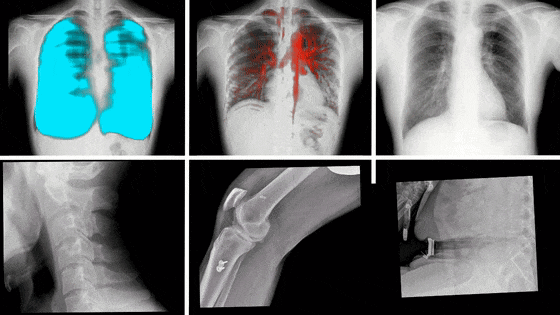

動態(tài)DR影像

動態(tài)DR,是近些年來迅速發(fā)展的影像技術(shù),其具備動態(tài)/靜態(tài)兩種模式,這意味著除了能像傳統(tǒng)靜態(tài)DR進(jìn)行普通的X片拍攝外,還能通過高幀率、多角度的采集技術(shù),捕捉拍攝部位的實時動態(tài),將短時間內(nèi)拍攝的數(shù)百張圖像合成為一個動態(tài)視頻。